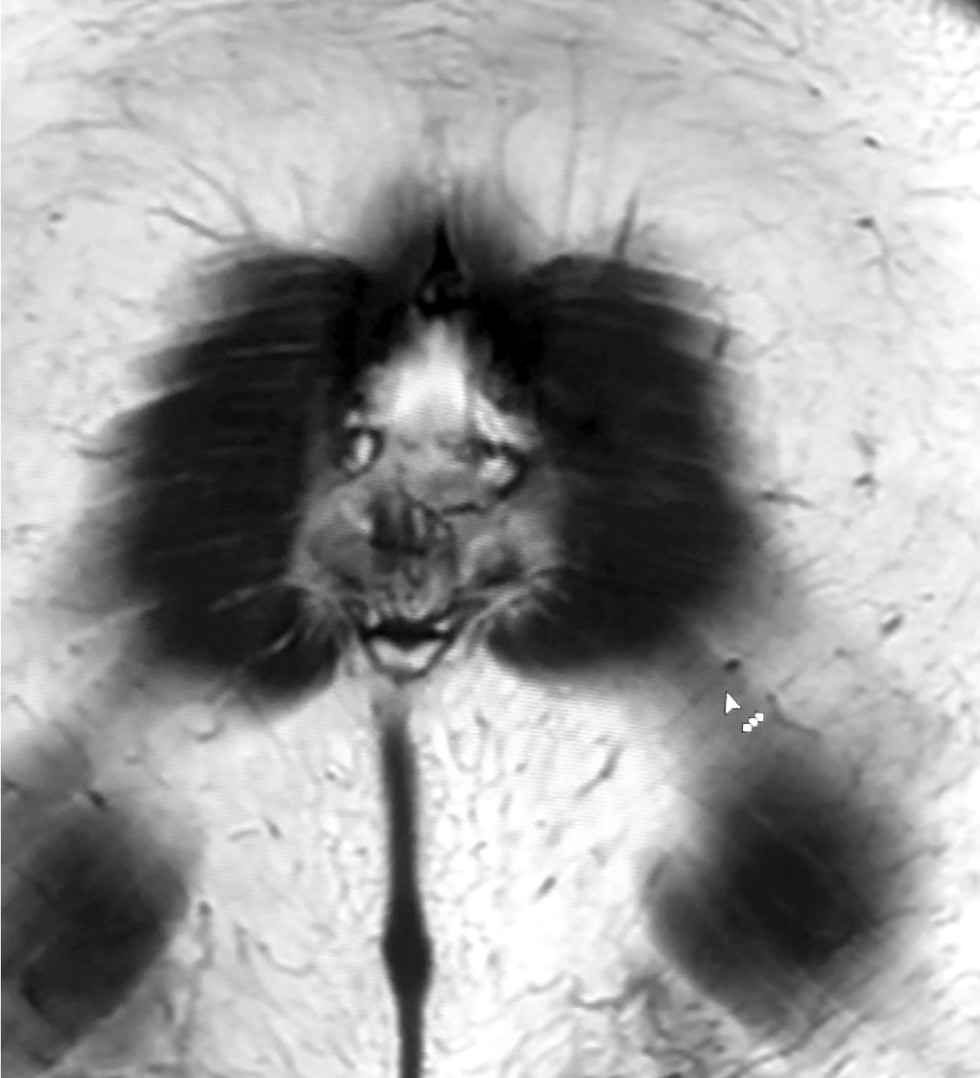

Visual images in radiography: pareidolia as a useful tool for physicians and artificial intelligence

This article explored the role of pareidolia in radiography and its potential in improving diagnosis and medical personnel training. Pareidolia is the phenomenon of perceiving familiar patterns in random objects, such as faces on the moon’s surface and animal figures in clouds. In radiography, pareidolia can manifest as recognizable patterns in medical images. This enables radiographers to identify abnormalities and improve their diagnostic skills.

This work aimed to evaluate pareidolia caused by the interpretation of X-ray images and determine its potential applications.

From June to December 2023, a competition was held to create a dataset of pareidolic illusions. Thirty-one individuals participated, including medical imaging specialists who had access to radiographic images. Images from nine additional participants were obtained outside the competition. Overall, 71 images were received. Participants uploaded images using a form on Yandex Forms. Data quality was ensured by clearly defined inclusion and exclusion criteria.

Data analysis revealed that people most frequently perceive human faces, animal snouts, and the heart symbol. These findings indicate the possibility of further research. This article discusses the potential applications of pareidolia in developing neural networks for automated medical image analysis and in educational activities that stimulate creative thinking and association.